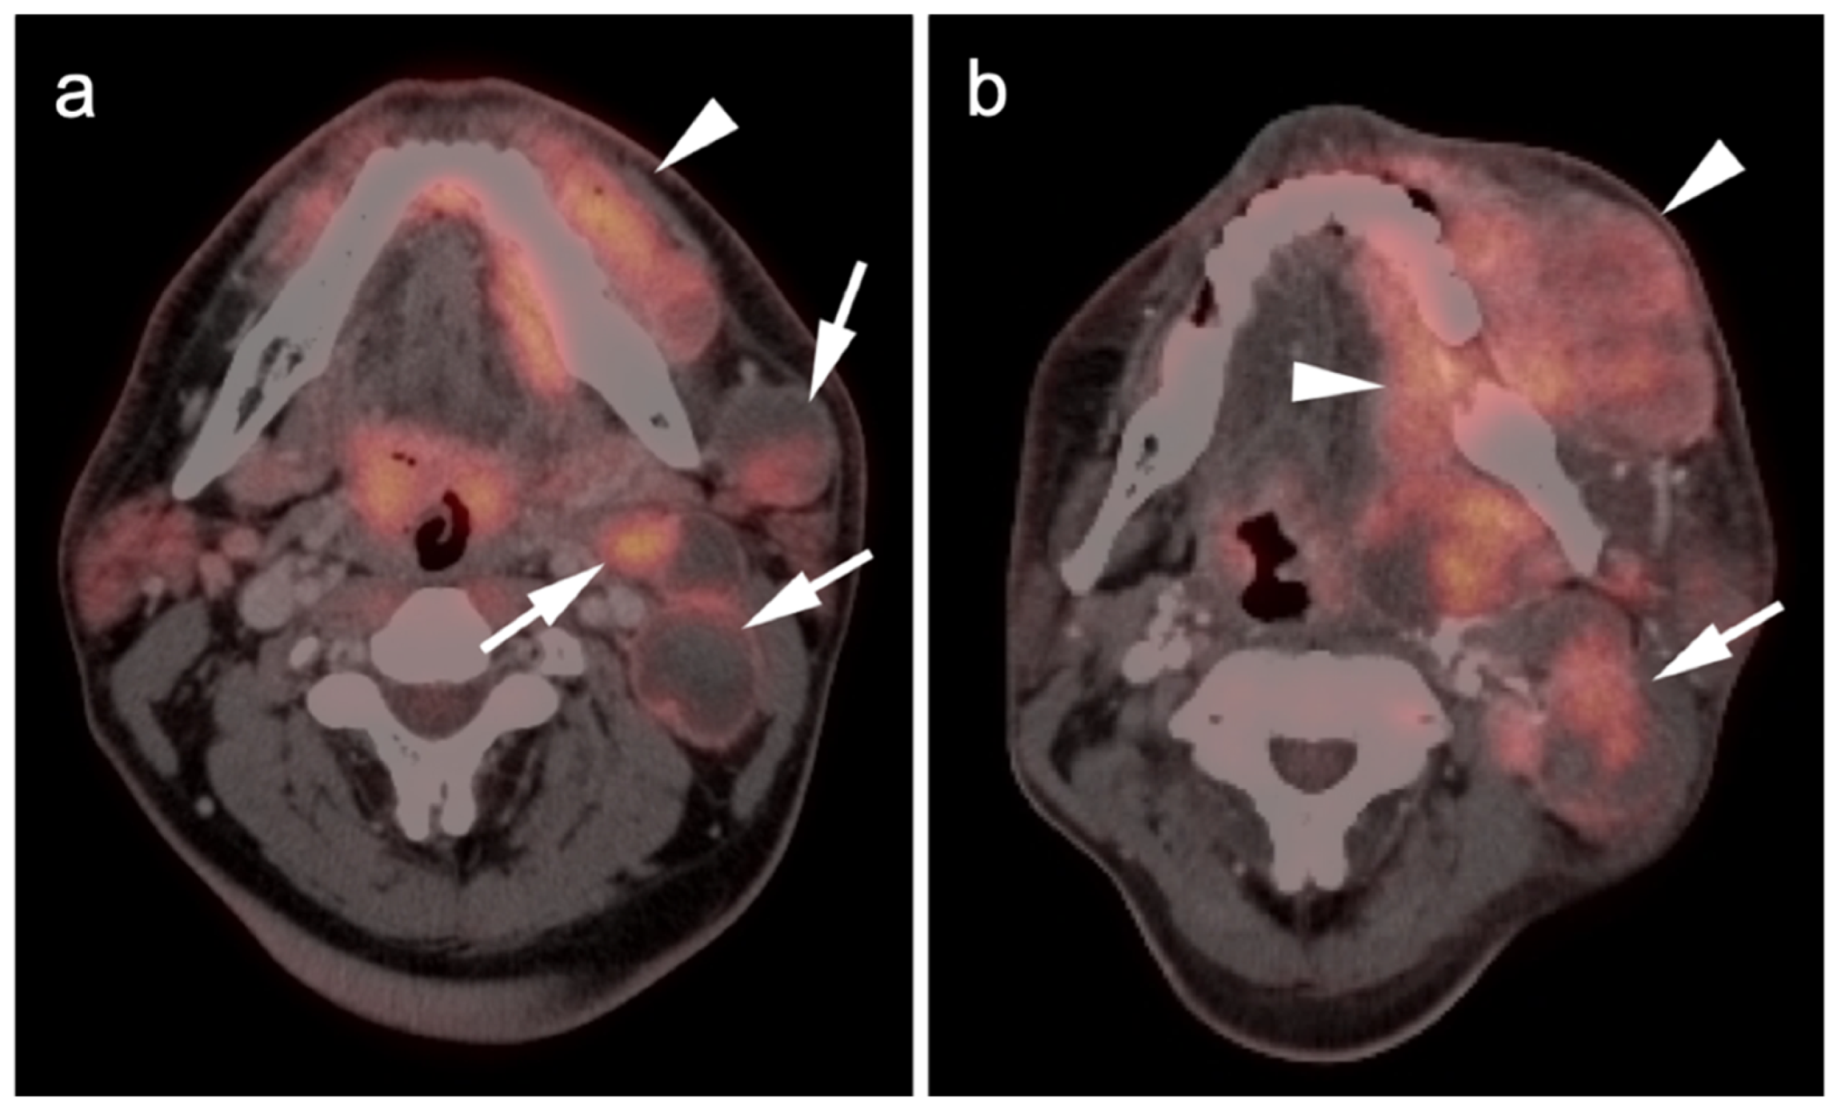

2.3.3. Mucosal Melanoma